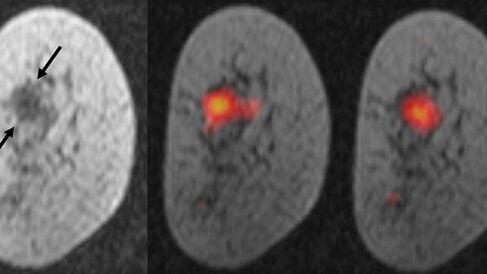

This is the first time researchers have demonstrated that this scanning technique, called carbon-13 hyperpolarised imaging, can be used to monitor breast cancer. The team based at the Cancer Research UK Cambridge Institute and the Department of Radiology, University of Cambridge, tested the technique in seven patients with various types and grades of breast cancer before they had received any treatment.

They used the scan to measure how fast the patients’ tumours were metabolising a naturally occurring molecule called pyruvate, and were able to detect differences in the size, type and grade of tumours – a measure of how fast growing, or aggressive the cancer is. The scan also revealed in more detail the ‘topography’ of the tumour, detecting variations in metabolism between different regions of the same tumour.